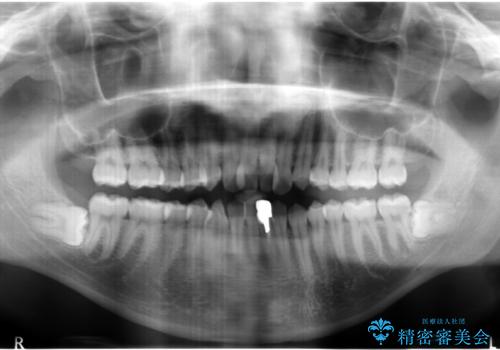

下の前歯は一本保険治療での被せ物になっており、変色していました。

・神経のない下の前歯を残す

・神経のない歯を抜いてしまって、天然歯で閉じる

のプランを提案し、神経のない前歯を抜く選択をされました。

下の前歯が3本になり奇数になることで、上下の真ん中は一致しませんが、そこまで目立たないと思います。

下の前歯の歯槽骨が一番薄く、歯肉退縮のリスクがあるため、今回のような1本抜歯も選択肢の一つです。